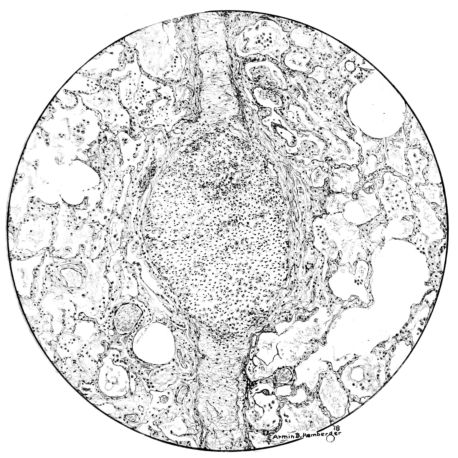

FIG. VII. AUTOPSY NO. 94. A NECROTIZING PROCESS LIKE THAT OF THE TRACHEA ILLUSTRATED IN FIGURE II. HERE IT IS SHOWN TO INVOLVE THE WALL OF THE BRONCHIOLE.

FIG. V. AUTOPSY NO. 95. AN EARLY LESION OF THE BRONCHIOLE CHARACTERIZED BY HYALINIZATION OF THE EPITHELIUM AND SEROUS EXUDATE IN THE LUMEN.

FIG. VI. AUTOPSY NO. 103. ILLUSTRATES ANOTHER EARLY BRONCHIOLAR LESION. THE EPITHELIUM IS LACKING, THE CONGESTED VESSELS OF THE SUBMUCOSA PROTRUDE INTO THE LUMEN WHICH CONTAINS DESQUAMATED EPITHELIUM, MUCUS, AND RED BLOOD CELLS.

15There is considerable evidence to support the view that the disease spreads from bronchus to bronchus, and in keeping with this view, various stages in the inflammatory processes are more readily determined in these smaller structures than in the trachea. Furthermore, it must be emphasized that even the mildest and the most extreme of these stages are not infrequently encountered in the same lung. The earliest lesion is manifested by an increased homogeneity of the protoplasm of the epithelial lining of the bronchus. The cell protoplasm loses its normal granulation and the nucleus, somewhat darker than usual, becomes conspicuous on a red base (Fig. V). In the lumen of such a tube a serous exudate, perhaps mixed with mucus, is encountered, and there is some spreading apart of the surrounding muscular tissue with engorgement of the vessels. This picture merges gradually into one where the epithelium appears as a homogeneous, red-staining ribbon, devoid of nuclei, often exfoliated, in part at least, from the underlying submucosa (92). The change is traceable through the larger bronchi, even to the ducti alveolares, and not infrequently, bacteria, either as a diffuse, minute dotting or in the form of circumscribed, colony-like formations, are spread through the red, ribbon-like strand (Fig. XVI). With the exfoliation of the epithelial lining, the submucous vessels become more and more conspicuous and may bulge into the lumen of the tube (Fig. VI). That they actually weep into the lumen is proved by the presence of red blood cells in the exudate, now rich in mucus, broken-down nuclei, and desquamated cells. The necrotizing process may not extend deeper than the epithelial lining as is the status described above (140, 162), but it also frequently involves the underlying submucous and muscular layers, so that these lose their identity and stand out as homogeneous masses, in which fragmented nuclei and bacterial accumulations are prominent. Such deeper necrotizing areas may be focal (Fig. VII), or may involve the entire circumference of the tube (Fig. VIII). Occasionally, the epithelium, now dead and staining homogeneously, is lifted from the underlying submucosa in the form of a blister (66), and has very much the same appearance as the well known, early reaction which follows the application of croton oil to the rabbit’s ear. Where this occurs, the submucosa is less involved, as though the necrotizing agent had not penetrated to the same depth and the serous reaction beneath were actually a beneficent exudate. These blisters are in contrast with the deeper areas where the fibrinous mass, mixed with the dead tissue, forms an intensely staining ring or band, which extends through the bronchiolar wall even to the surrounding alveoli.